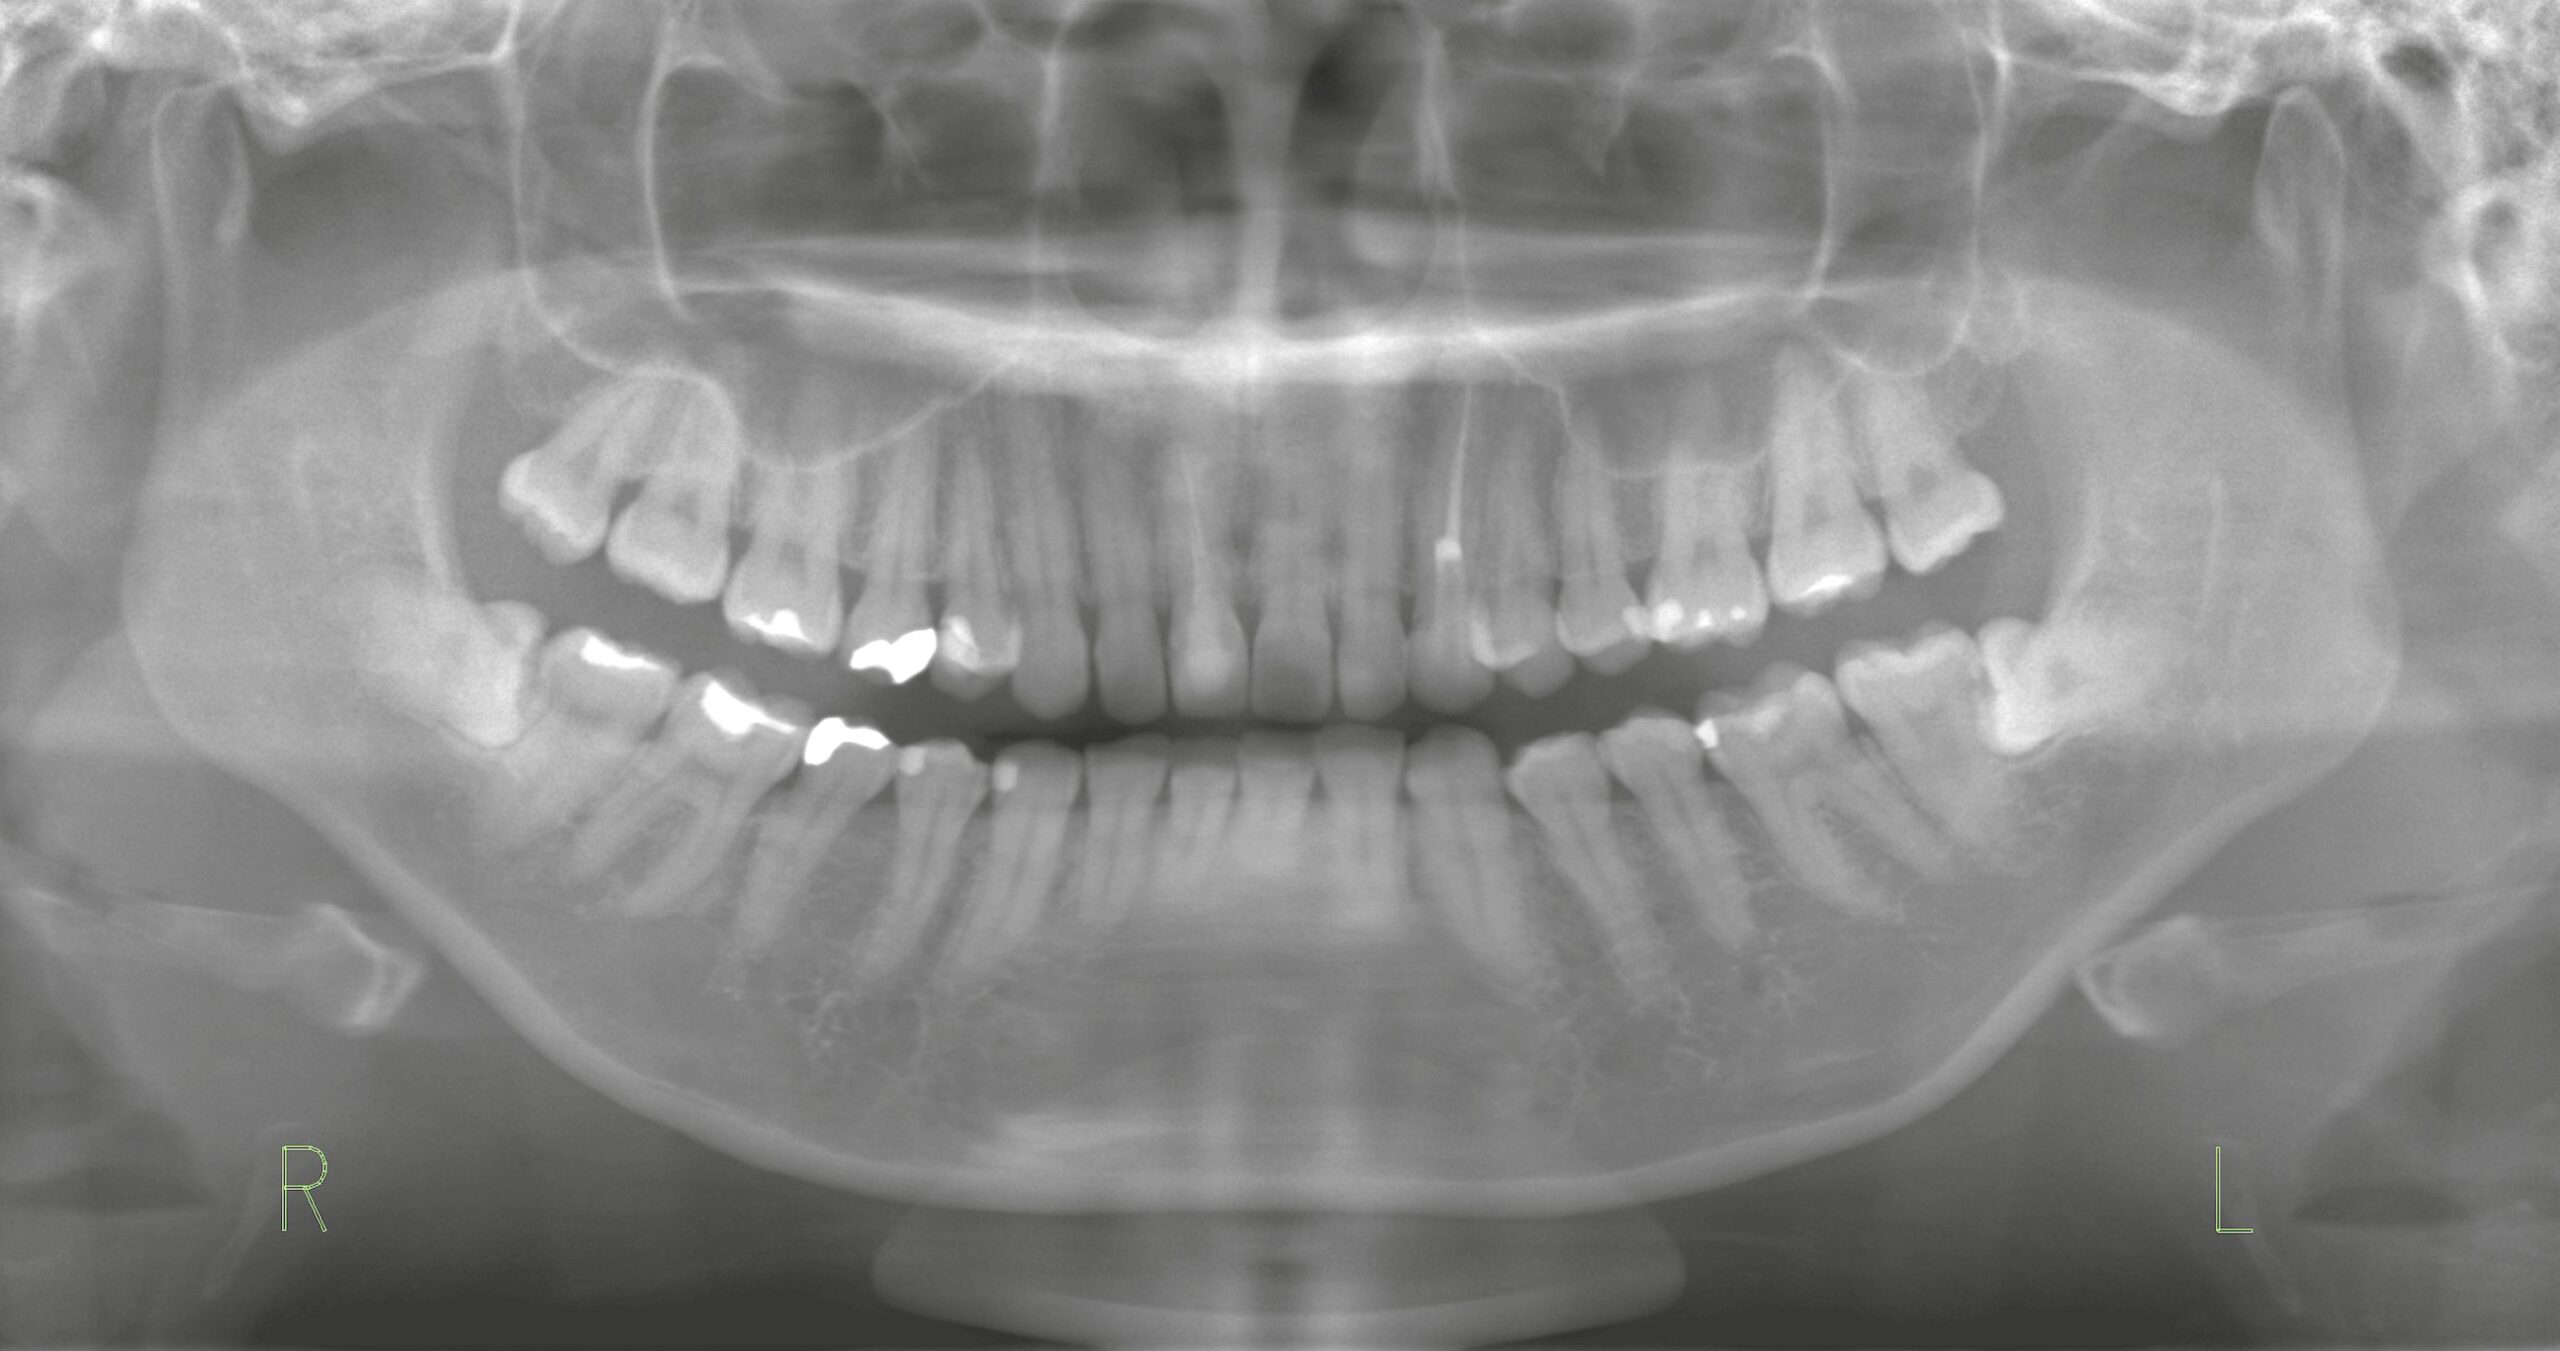

診断にはレントゲン・CTによる詳細な評価が不可欠であり、清掃状態や全体の咬合関係を含めて総合的に判断することが求められます。